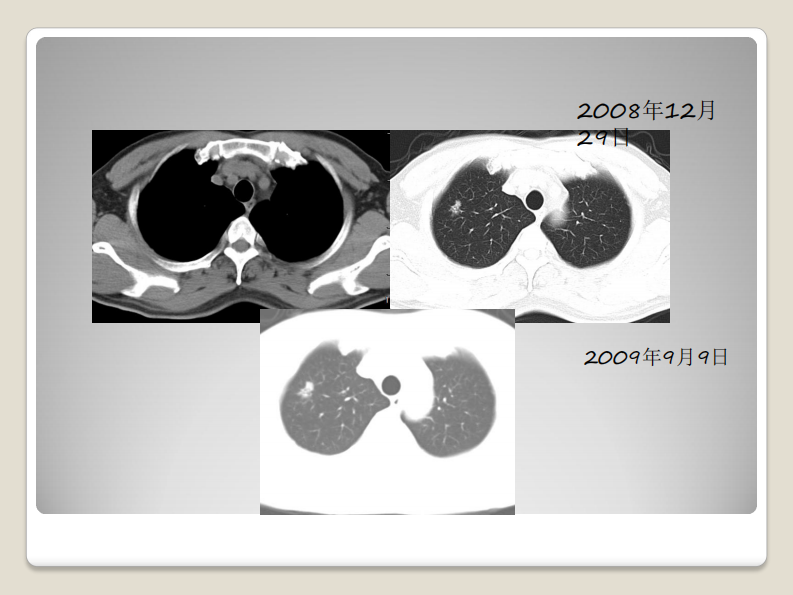

磨玻璃结节的影像分析--郭亮.pdf